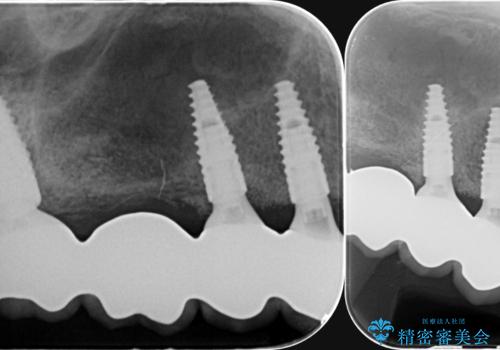

X線写真検査より、根尖病変に加え、歯周病による歯槽骨の吸収も見られ、歯質も薄く保存は難しいと判断し、

インプラント治療を進めることとなりました。

- 165万円(インプラント×3・チタンカスタムアバットメント×3・ジルコニアクラウン×4・仮歯×6)費用は治療当時の料金となります